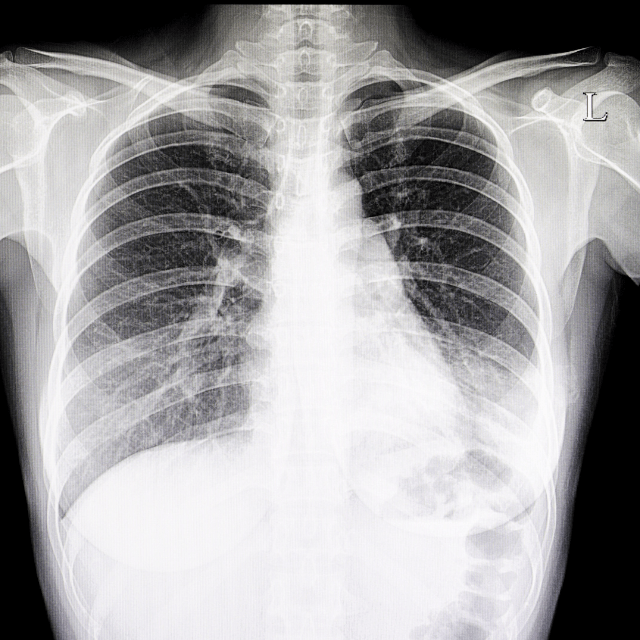

マイコプラズマ肺炎